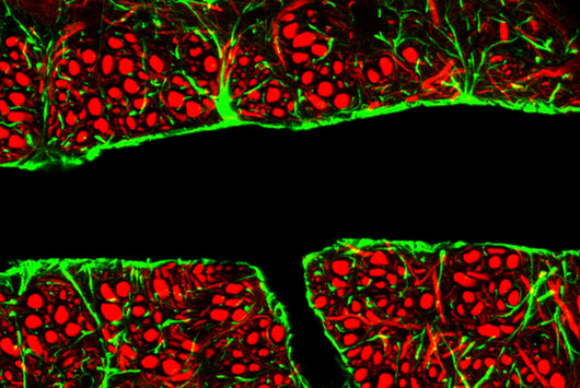

مقطع لوعاء دمويّ في الدّماغ (بالأسود)، تحوي جدرانه الخلايا البطانيّة المتكاتفة. تحيط به الخلايا الدّبقية (بالأخضر) والخلايا العصبيّة (بالأحمر). الحاجز الدّموي الدّماغيّ | المصدر: C.j.guerin, Phd, Mrc Toxicology Unit, Science photo Library

يتكوّن الحاجز الدّموي الدّماغيّ بفضل المبنى الخاصّ للخلايا البطانيّة في الأوعية الدّمويّة التي في النّسيج الدّماغي. الخلايا البطانيّة هي طبقة الخلايا التي تغطّي جدران الأوعية الدّمويّة في الجسم. تنتظم هذه الخلايا في الدّماغ في مبنى متكاثف جدًّا، يُعيق مرور الجزيئات من خلاله ويُسمّى "التقاطع الضيّق بين الخلايا". لا توجد في خلايا الدّماغ البِطانيّة ممرّات وقنوات تتيح انتقال الجزيئات من الدّم إلى الأنسجة المجاورة، وذلك بخلاف الخلايا البطانيّة في سائر أنحاء الجسم، التي تتيح انتقال الجزيئات من الدّم إلى الأنسجة المجاورة بحريّةٍ تامّة. يتمُّ بهذه الطريقة الفصل الدّائم بين الدّماغ والموادّ التي تمرّ عبر الدورة الدمويّة.